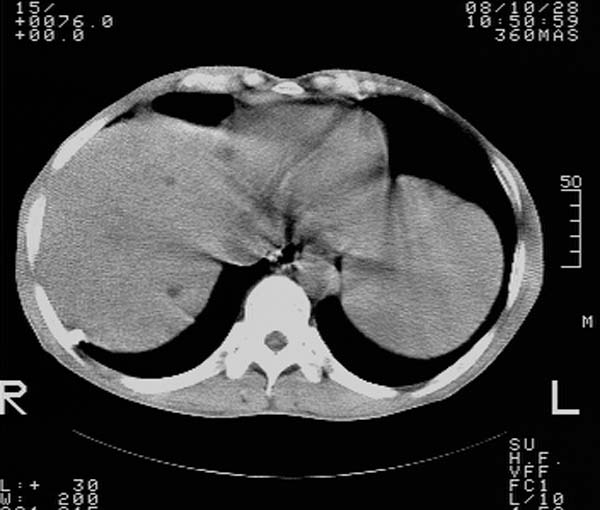

m,65y。半年前发现颈小结节,逐渐增多增大,现双侧耳后、颌下及颈部表浅淋巴肿大。胸片示双肺门增大。外院曾穿刺诊断为淋巴结核。在我科作胸腹部ct,我们觉得外院病检有误。现将图像上传请战友讨论。

纵隔内及腹膜后广泛淋巴结肿大,脾大,肝内似可见低密度影,结合病史半年前发现颈小结节,逐渐增多增大,现双侧耳后、颌下及颈部表浅淋巴肿大。考虑淋巴瘤。

我们也是首先考虑淋巴瘤。只是外院病检报告是结核。让人迷惑。肝左叶多发低密度占位,没增强不好定论。

纵隔,双肺门腹膜后多发淋巴结重大,非融合,肝脾轻度肿大,双肺野弥漫性小结节;考虑淋巴瘤,结节病可能性

纵隔内,双肺门、腋窝及腹膜后多发肿大淋巴结影,肺内小结节影,肝脾体积增大,支持淋巴瘤。肝内多发低密度影,考虑小囊肿。

考虑淋巴瘤肺、肝内转移,脾脏肿大。

纵隔内,双肺门、腹膜后多发肿大淋巴结影及颈部淋巴结肿大,肝脾体积大.结合临床,淋巴瘤可能性大。